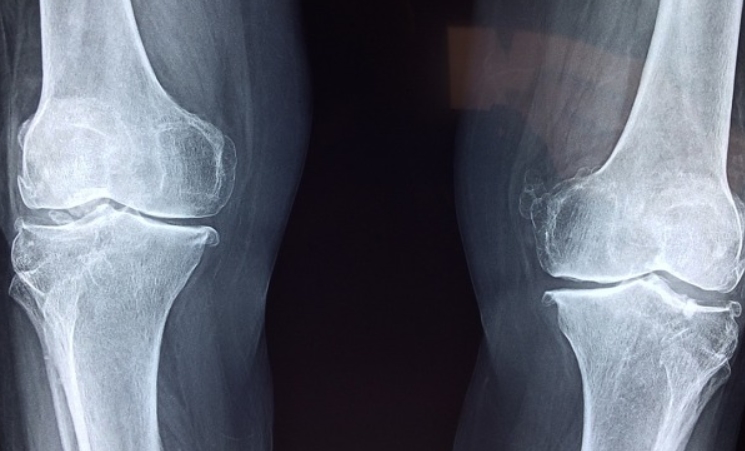

- X-ray, MRI, 초음파 검사: 관절 손상 여부를 확인하기 위해 촬영하는 검사입니다.

이러한 검사를 통해 류마티스 관절염 초기증상을 확진할 수 있으며, 이후 치료 방향을 결정하게 됩니다. 저는 검사 후 결과를 기다리는 동안 긴장됐지만, 결과를 빨리 알고 적극적으로 대처하는 것이 중요하다는 것을 느꼈습니다.